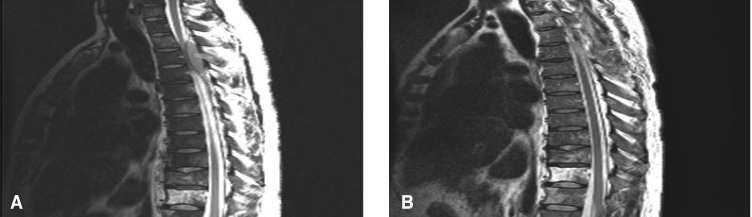

A 40-year-old man was hospitalized due to jaundice and lethargic fatigue that started 10 days prior to admission. The patient had complaints of weight loss and night sweats. Four months prior to this admission, he had visited to the Department of ENT at another hospital with the complaint of nasal stuffiness. At that time, the serologic testing for hepatitis B antigen and anti-HIV antibody were positive. He has been treated with zidovudine, lamivudine and efavirenz for two months until admission. He assumed that his AIDS was transmitted from heterosexual contact at abroad ten years ago. On admission, the blood pressure was 120/70 mmHg, the pulse rate 90/min, the respiratory rate 20/min and the body temperature was 36.6℃. He was icteric on the physical examination. The liver was tender and firm in consistency. It was palpated at a three-finger breadth below the right costal margin. His spleen and lymph nodes were not enlarged. The laboratory results were normal apart from an ESR of 120 mm/h; leukopenia 3,930/mm3 (neutrophils: 58.8%, lymphocytes: 31% and monocytes: 8.4%) and hemoglobin 9.4 g/dL. The liver function tests were abnormal: total bilirubin 8.9 mg/dL (direct bilirubin: 6.05 mg/dL), AST 171 IU/L, ALT 100 IU/L and LDH 1063 IU/L. The total number of CD4 and CD8 T lymphocytes was 290/mm3 and 568/mm3, respectively, and the ratio of CD4/CD8 was 0.51. Abdominal enhanced CT scanning revealed multifocal and variable sized homogenous hypodense masses in both hepatic lobes (Figure 3). A liver biopsy showed a heavy infiltration composed mainly of large lymphoid cells (Figure 4A). Immunohistochemical staining revealed the atypical cells to be CD20 positive (Figure 4B), which established a diagnosis of diffuse large B-cell lymphoma according to the WHO classification. Bone marrow biopsy demonstrated normal cellularity with normal maturation of all three cell lines. There was no malignant cell infiltration. After the patient was diagnosed as having diffuse large B-cell lymphoma, he received VAD (vincristine 0.4 mg, adriamycin 9 mg/m2, dexamethasone 40 mg on days 1-4, and additional dexamethasone on days 9-12 and days 17-20). The patient seemed to show a little clinical improvement, but before starting the second chemotherapy, he developed signs of spinal cord compression (Figure 5A). Emergency radiation therapy was delivered to the spine lesion. CHOP chemotherapy (cyclophosphamide 750 mg/m2, adriamycin 50 mg/m2 and vincristine 1.4 mg/m2 on day 1 and prednisone 100 mg/m2 on days 1-5) and laminectomy induced temporary improvement (Figure 5B). Alas, the paraplegia continued and his clinical condition progressively worsened. He passed away 103 days after starting the second round of chemotherapy from complications of pressure sores, deep vein thrombosis and pulmonary thromboembolism.

(A) The initial D-spine MRI shows the signal intensity of the entire vertebral body is diffusely decreased with heterogeneous enhancement at the D9 to D11 vertebral bodies after gadolinium injection. An elongated posterolateral epidural mass is seen at the D2 through D4 levels, which causes severe cord compression. (B) After radiotherapy and chemotherapy, the follow up MRI revealed marked regression of epidural mass and cord compression at the D2-4 level.